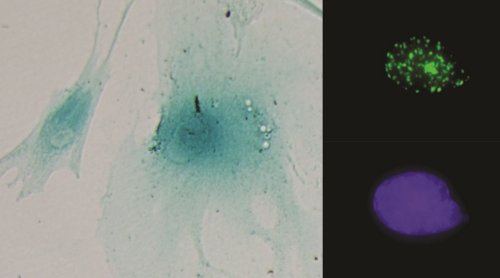

Izquierda: células senescentes. Derecha: núcleo celular mostrando foco de daño al ADN (arriba) y su control (abajo). (Imágenes: CIBER)

Según explica Amancio Carnero, “la senescencia consiste en una parada de la división celular de las células que lo sufren, pese a lo cual estas son capaces de secretar una serie de factores que aumentan la capacidad tumorigénica de las células tumorales. Esto provoca que se establezca un circuito entre células tumorales y las que no lo son, que conduce a un aumento del número de células madre tumorales, las cuales poseen una capacidad proliferativa mayor que las células tumorales normales y son capaces de aumentar la resistencia a terapias antitumorales”.